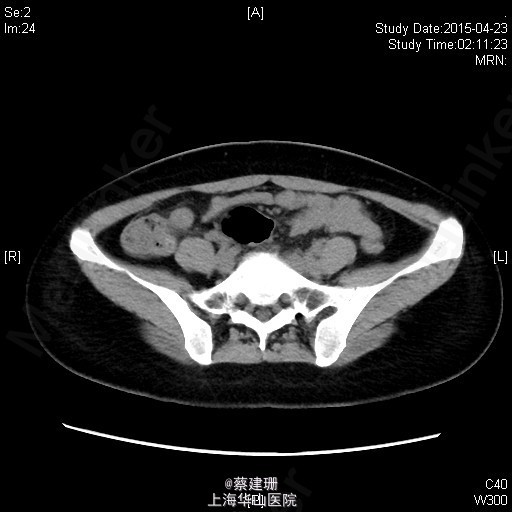

急性阑尾炎(粪石?)伴局限性腹膜炎

患者 女性 24岁,因“转移性右下腹痛一天余。”入院。患者一天前无明显诱因下出现中上腹疼痛,无恶心呕吐,无腹泻。10小时前疼痛转移至右下腹,原先中上腹疼痛缓解,无发热无腹泻。患者未予重视,后疼痛难忍于今日凌晨至我院急诊就诊,血常规示:WBC:18.63*10^9/L,我院B超示:右下腹见肠段局限性扩张,炎性病灶待排。肝胆胰脾肾未见明显异常,双输尿管未见扩张。我院CT示:阑尾增大壁增厚内见高密度影及低密度气体影,符合阑尾炎改变,盆腔少量积液。患者拒绝行急诊手术,故予以保守治疗,患者症状未缓解,右下腹疼痛加重。为行进一步诊治,收入院。

全身皮肤粘膜未见异常,无肝掌,全身浅表淋巴结无肿大。腹平坦,腹壁软,右下腹压痛,伴有肌紧张及反跳痛,麦氏点压痛(+),肝脾肋下未触及,肝肾脏无叩击痛,肠鸣音4次/分。 辅助检查:血常规示:WBC:18.63*10^9/L,N:89%。我院B超示:右下腹见肠段局限性扩张,炎性病灶待排。肝胆胰脾肾未见明显异常,双输尿管未见扩张。我院CT示:阑尾增大壁增厚内见高密度影及低密度气体影,符合阑尾炎改变,盆腔少量积液。

入院后诊断:急性阑尾炎伴局限性腹膜炎。完善相关检查,全麻下行腹腔镜下阑尾切除术。术后恢复可,伤口无明显渗出,予以出院。